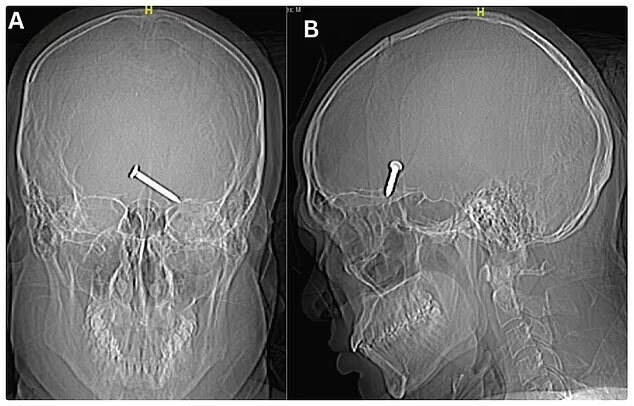

Строитель поступил в больницу в сознании. Мужчина объяснил ситуацию и пожаловался на боль в глазу и слепоту. Врачи сделали ему прививку от столбняка и поставили капельницу с антибиотиками, а после отправили на рентген.

На снимках было видно, что гвоздь размером 3 см застрял в лобной доле мозга строителя, которая отвечает за движение и речь. Однако мужчине повезло — важные нервные окончания задеты не были.

Гвоздь из глаза пациента достали хирургическим путём, а через 5 дней мужчину выписали из больницы. Медики добавили, что им удалось сохранить зрение пострадавшему.